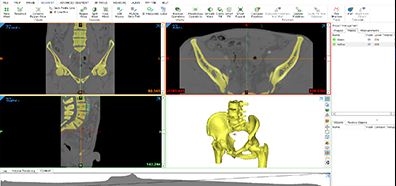

3D Segmentation 의뢰 및 라이센스 대여

CT, MRI 등 의료 영상에서 원하는 부이(뼈, 혈관, 장기)를 선택적으로 Modeling 해 장기 Volume, 각족 수술 전후 Measurment 측정, 3D프린터 등 다양한 분야에서 활용

Mimics

3D 모델링 소프트웨어

의료용 CAD 소프트웨어로 수술용 가이드, 보조기 등 제작

-

Mimics 3-matic